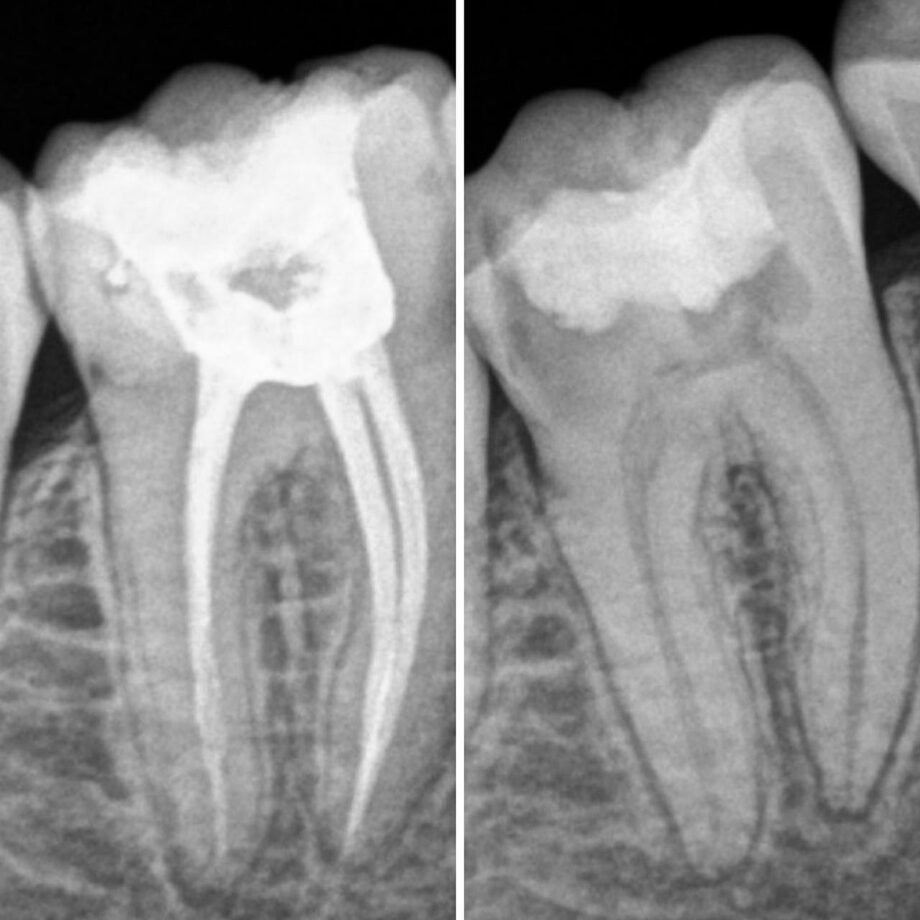

До и после лечения пульпита

Для лечения острого и хронического пульпита чаще всего предполагает удаление воспаленного нерва зуба и инфицированного дентина в канале зуба. Проводится под местной анестезией. Врач после вскрытия полости, снятия пораженных тканей и удаления нерва проводит орошение каналов зубов антисептическими растворами и обработка каналов специальными инструментами, высушивание и пломбирование каналов. После пломбировки каналов вам устанавливается временная пломба и пациент уходит, чтобы паста застыла. На следующем приеме принимается решение, каким образом лучше всего восстановить зуб. Чтобы восстановить целостность сильно разрушенного зуба применяются зубные вкладки, которые затем покрываются коронкой. Если стенки зуба сохранились, то возможна терапевтическая реставрация зуба.